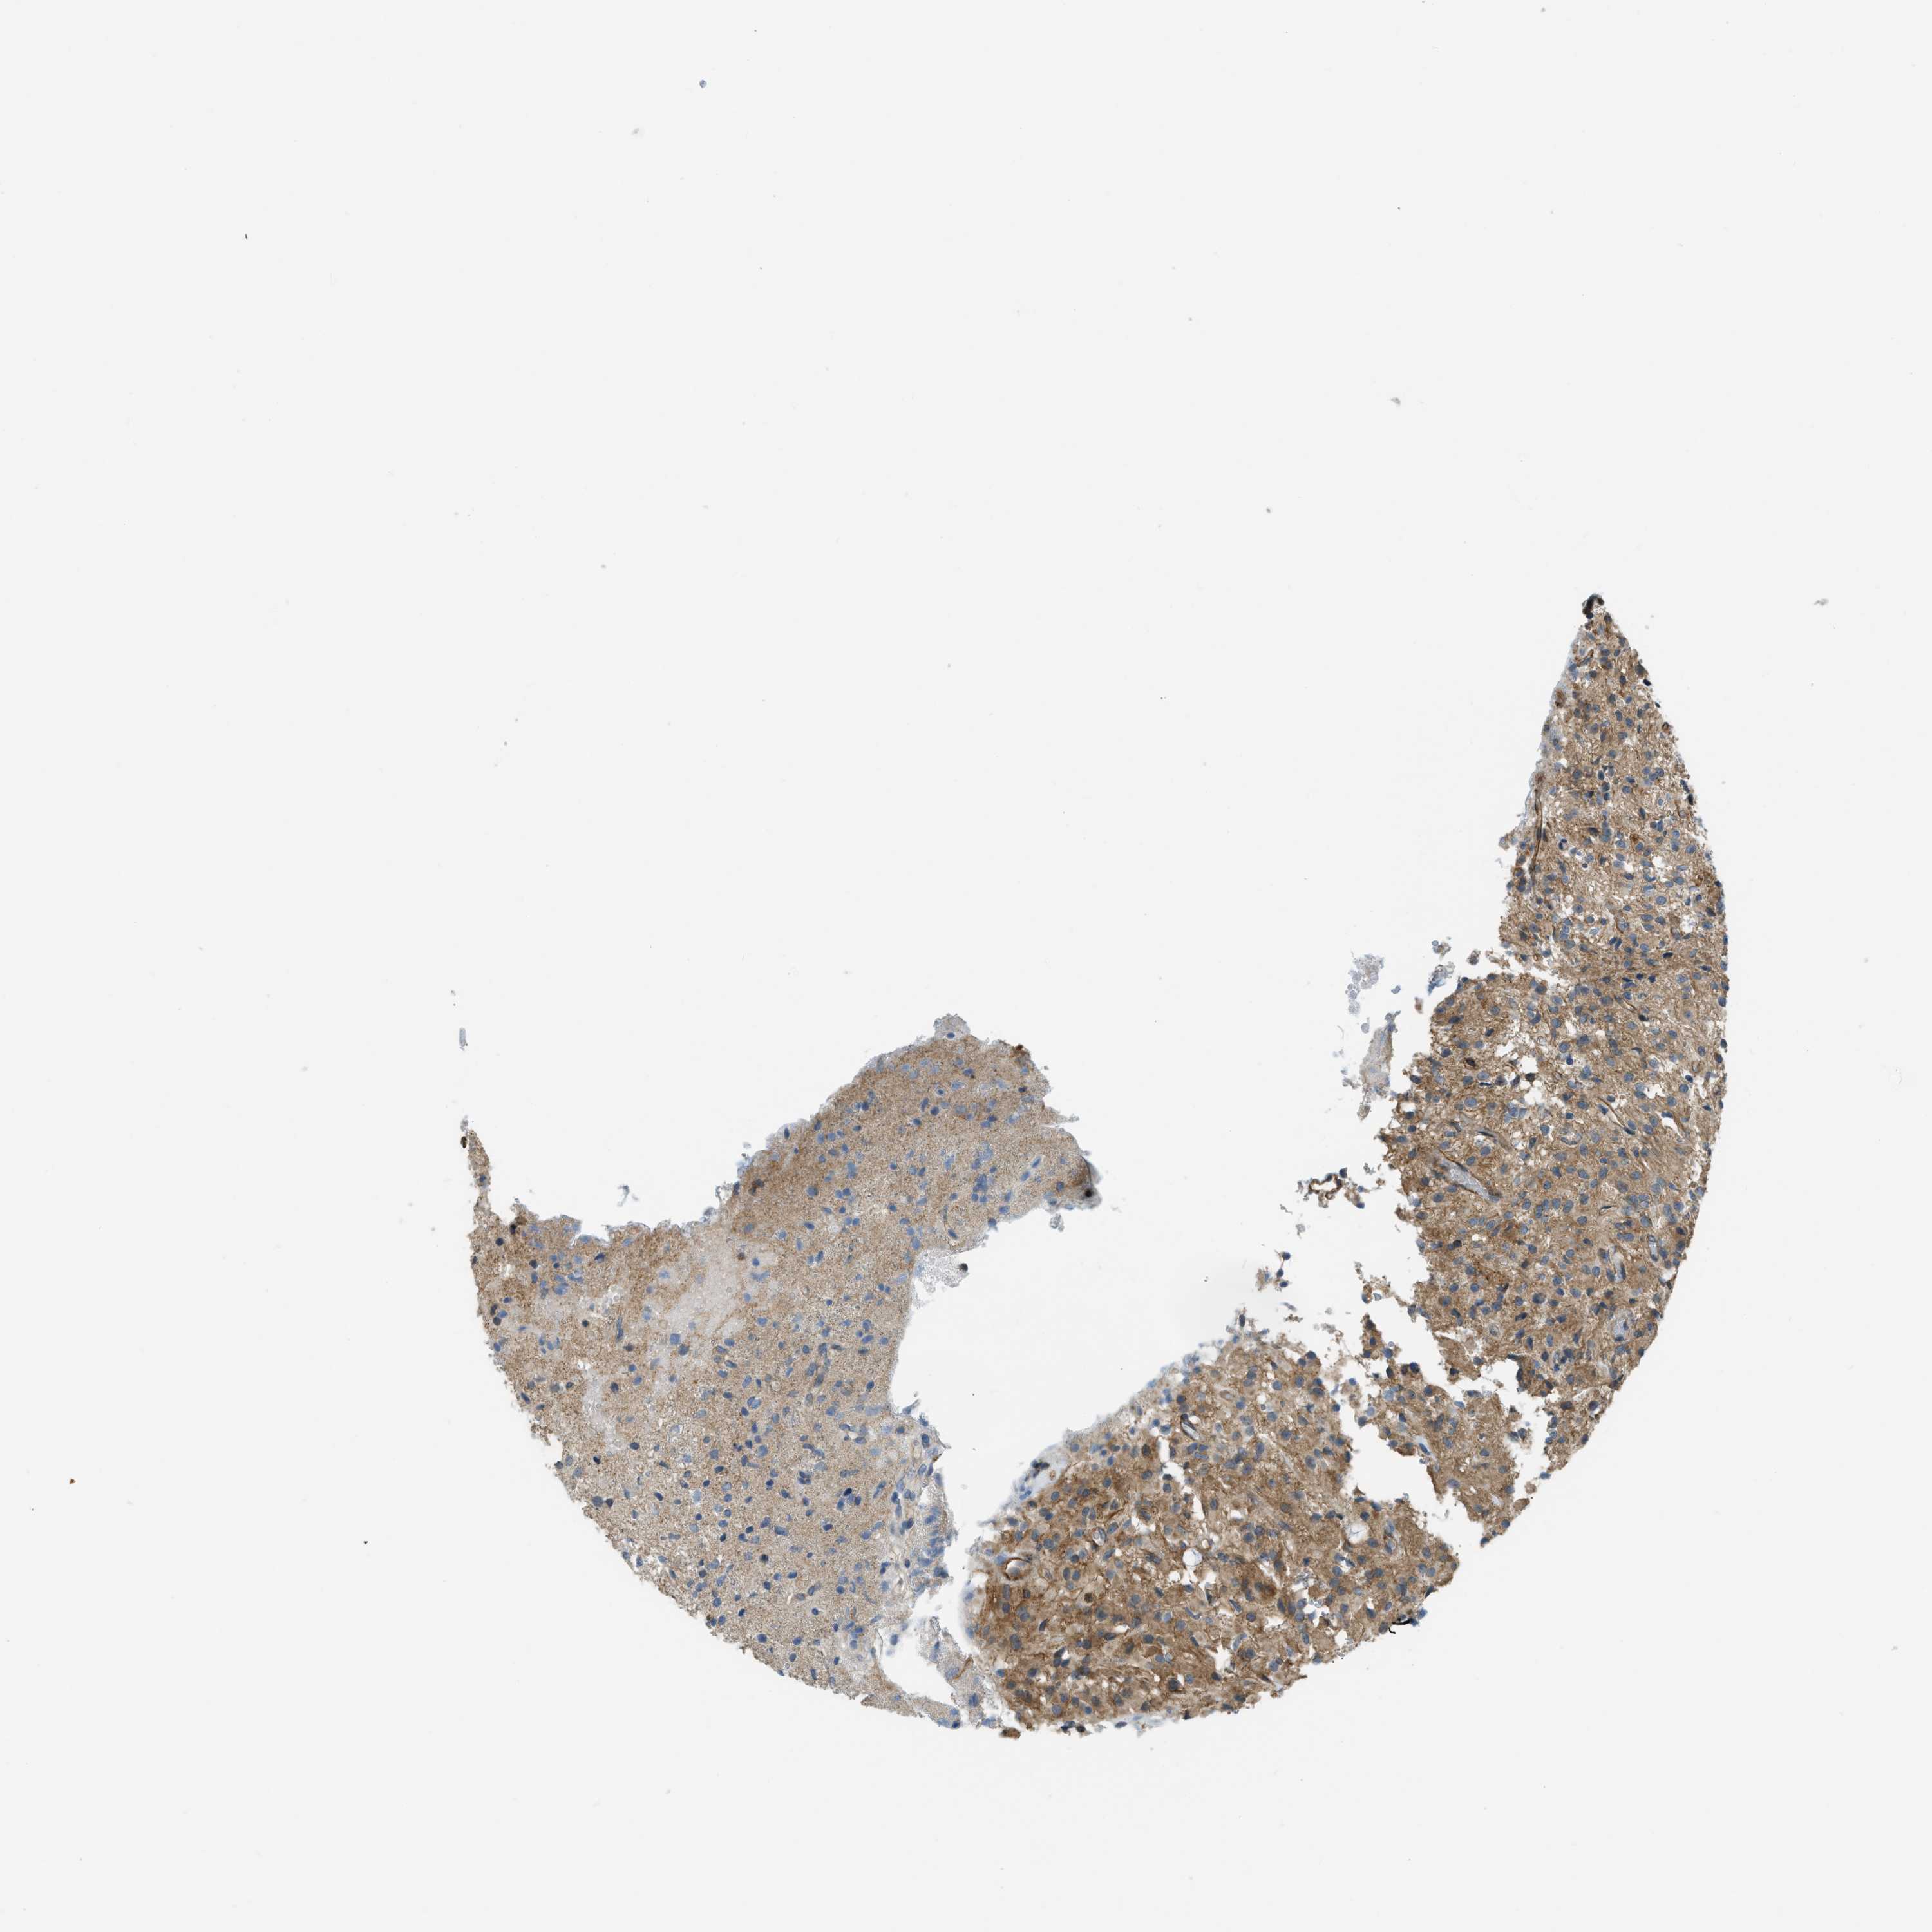

GLIOMA - Protein expressioni

A mouse-over function shows sample information and annotation data. Click on an image to view it in a full screen mode. Samples can be filtered based on level of antibody staining by selecting one or several of the following categories: high, medium, low and not detected. The assay and annotation is described here.

Note that samples used for immunohistochemistry by the Human Protein Atlas do not correspond to samples in the TCGA dataset.

Antibody stainingi

Antibody staining in the annotated cell types in the current human tissue is reported as not detected, low, medium, or high, based on conventional immunohistochemistry profiling in selected tissues. This score is based on the combination of the staining intensity and fraction of stained cells.

Each image is clickable and will lead to virtual microscopy that enables deeper exploration of all samples and also displays staining intensity scores, fraction scores and subcellular localization as well as patient and tissue information for each sample.

Antibody HPA018135

Staining

High

Medium

Low

Not detected

Intensity

Strong

Moderate

Weak

Negative

Quantity

>75%

75%-25%

<25%

None

Location

Nuclear

Cytoplasmic/membranous

Cytoplasmic/membranous,nuclear

Glioma, malignant, High grade

Glioma, malignant, Low grade